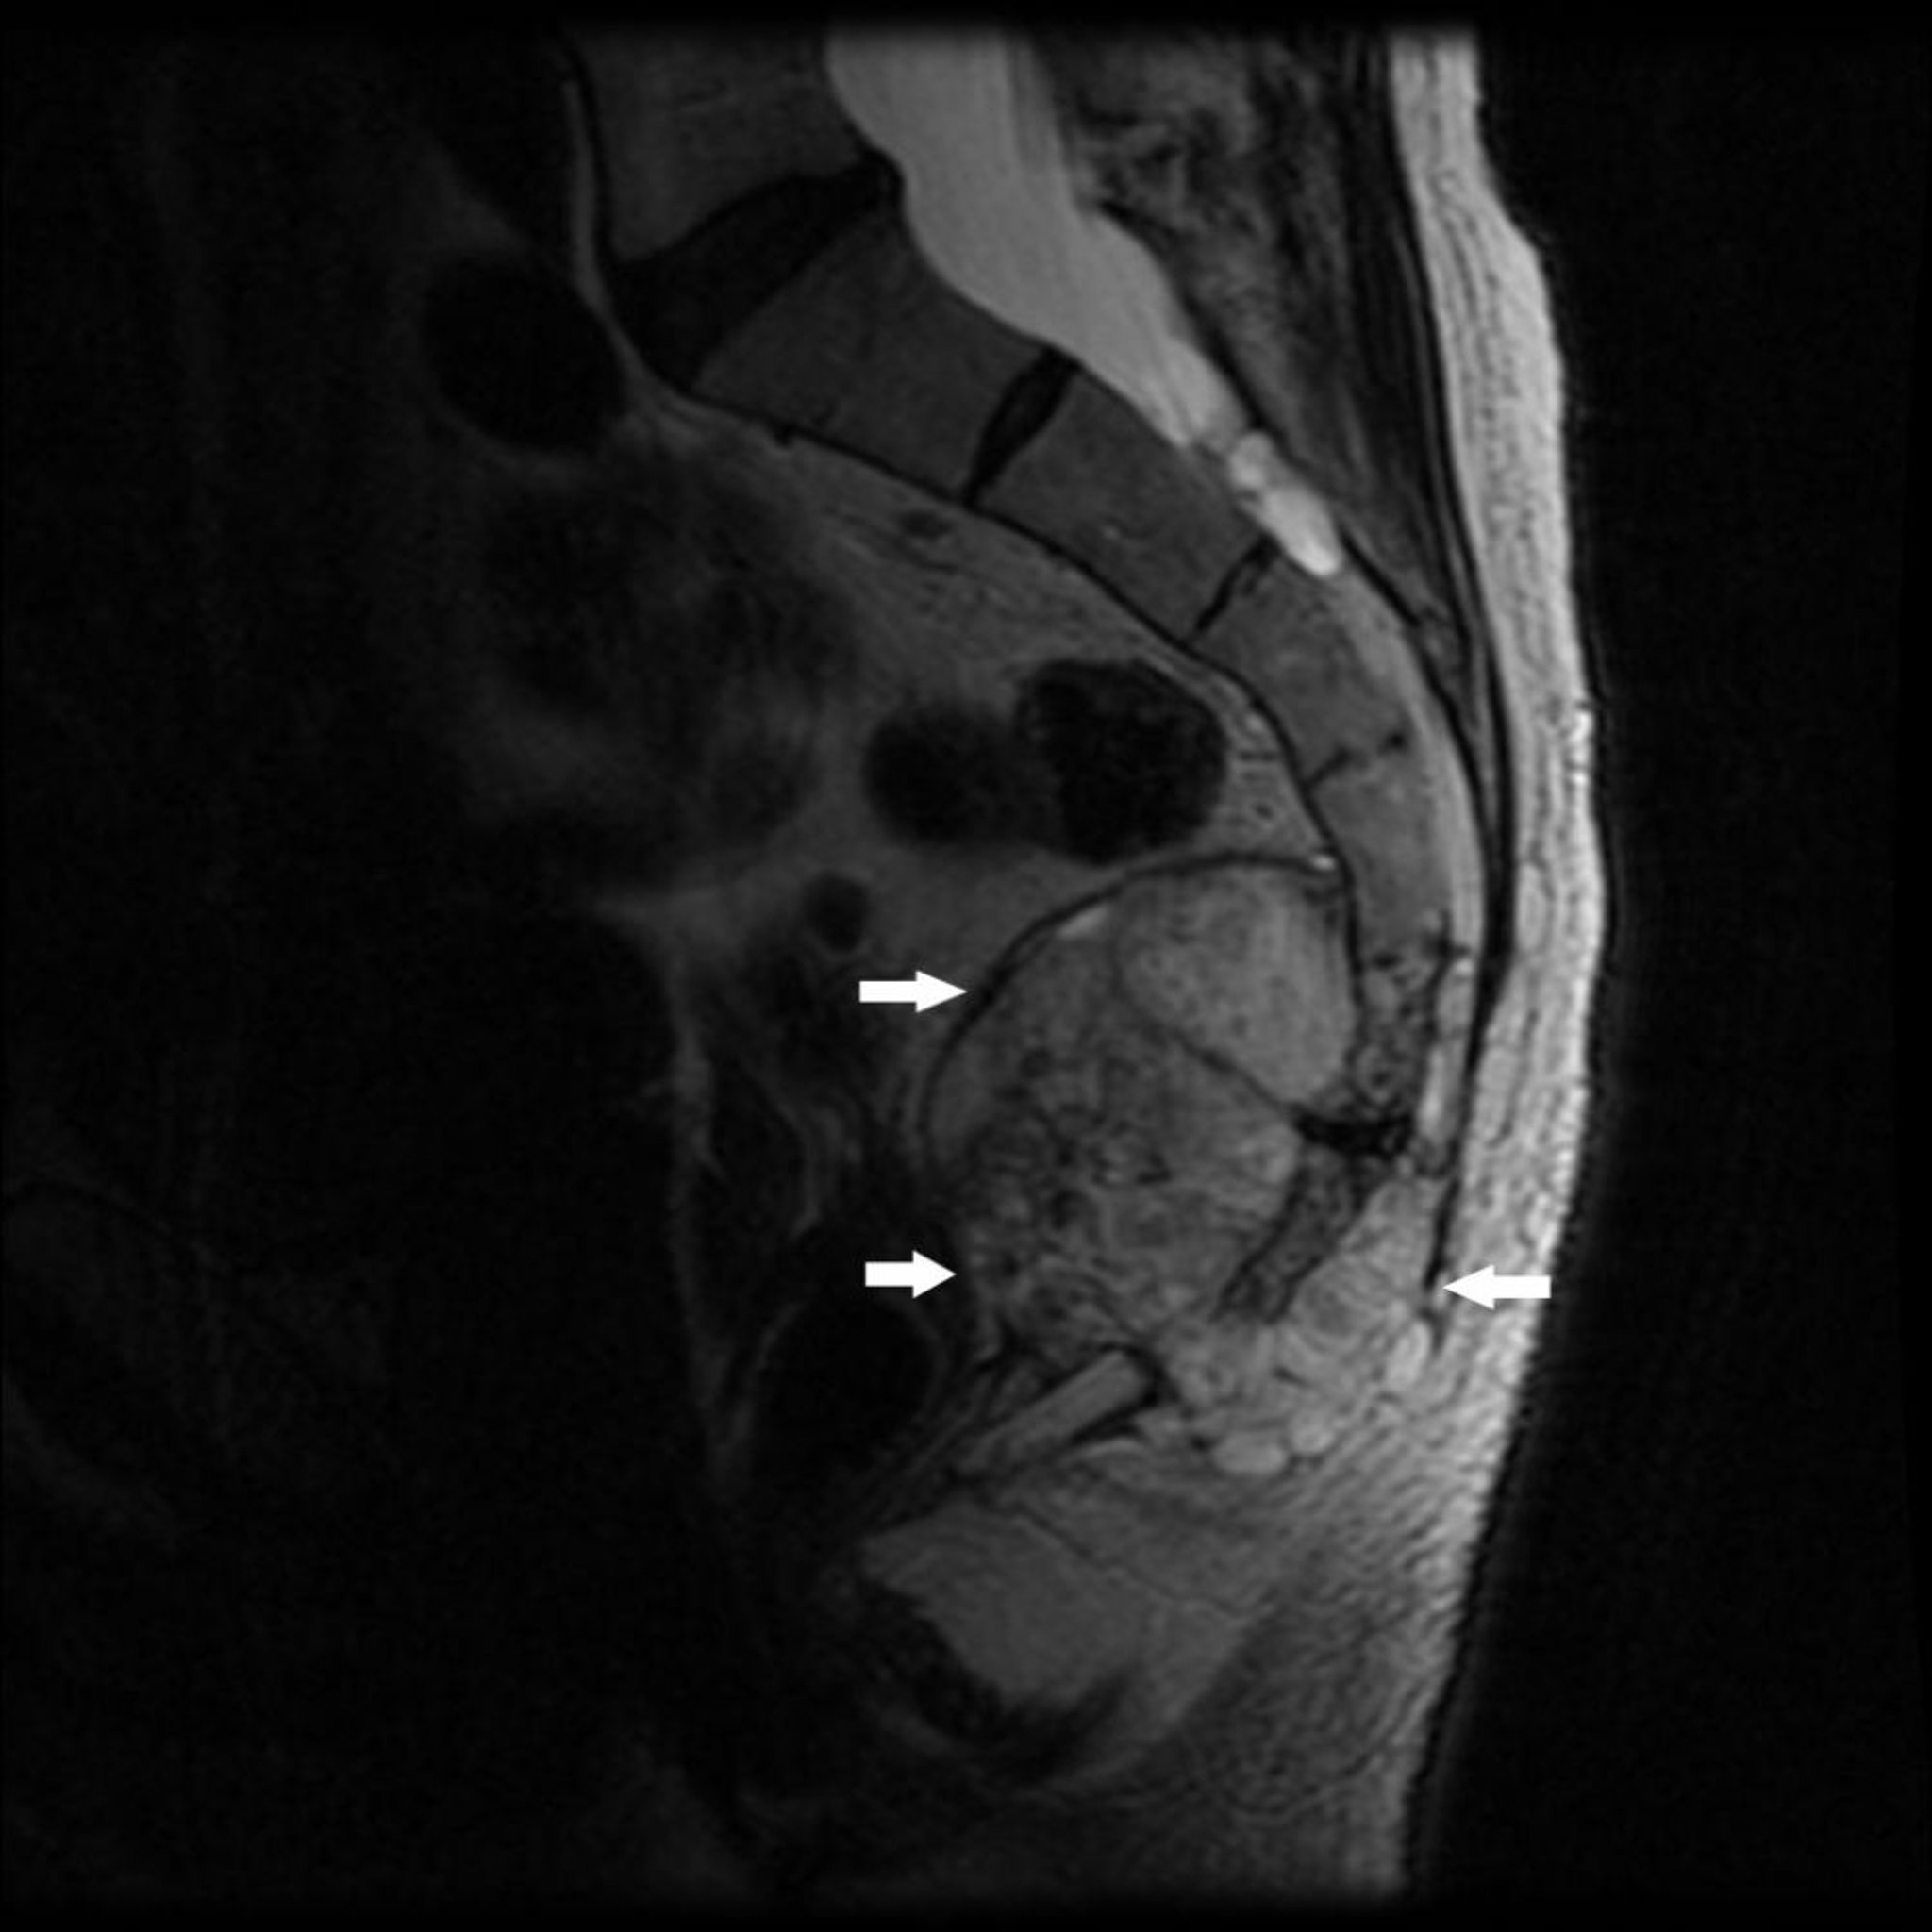

Esta RM muestra un tumor en el extremo caudal del sacro (S4) y cóccix con destrucción ósea y masa de tejido blando (flechas), característica de un cordoma.

Image courtesy of Michael J. Joyce, MD, and Hakan Ilaslan, MD.